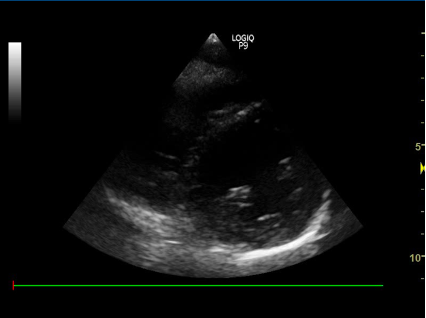

3) Parasternalt længdesnit:

- Nævn strukturerne:

proben skal pege mod patientens hø. skulder